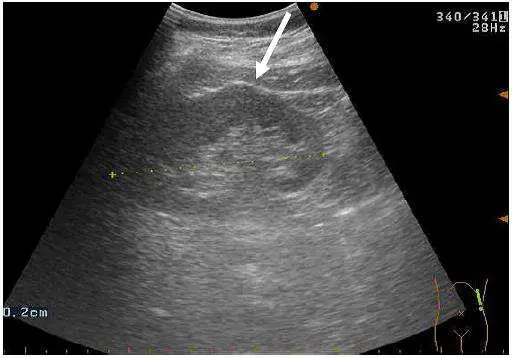

附圖中腎臟凸出之處(箭號所指)為下列何者?

影像顯示一個腎臟的超音波掃描,白色箭號指向腎臟上方輪廓一處明顯的局部凸出(focal bulge)。主要影像特徵如下:

- 位置:凸出位於腎臟外側(lateral)上緣,即腎臟輪廓的上外側邊界

- 回音性(echogenicity):凸出區域的回音性與相鄰腎實質(renal parenchyma)完全相同,無回音增強或減弱,無邊界不清或不均質改變

- 形態:平滑的弧形凸出,與正常腎臟輪廓連續,無突兀分界

- 無佔位效應:無腎竇(renal sinus)受壓或變形的跡象

- 測量標記:影像下方可見測量卡尺(calipers),顯示此為左腎(與脾臟位置相鄰的腎臟)

上述特徵高度符合駱駝峰(dromedary hump):即因左腎緊鄰脾臟,受脾臟長期壓迫塑形所致的外側輪廓局部凸出,屬正常解剖變異。